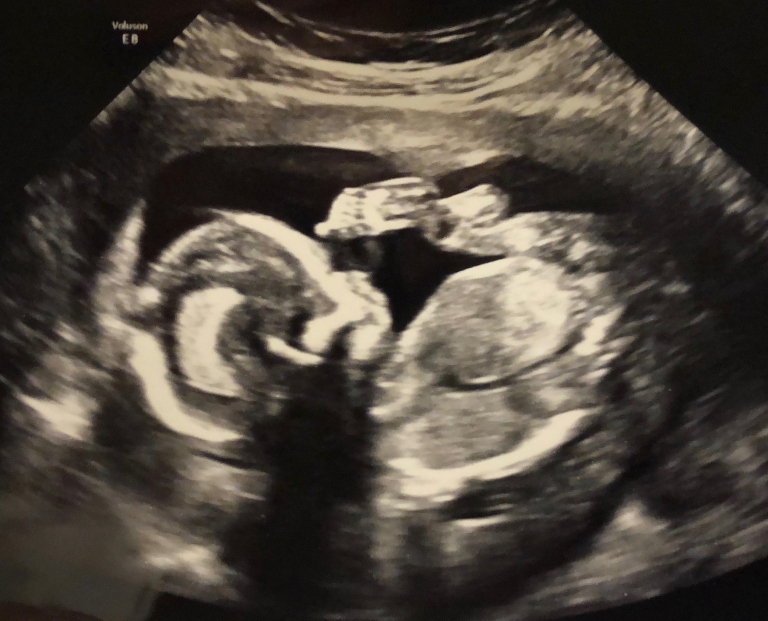

Gaby tikt op het uur de 24 weken aan met haar tweeling, pfff, maar wat er dan allemaal gebeurt had niemand verwacht DEEL II